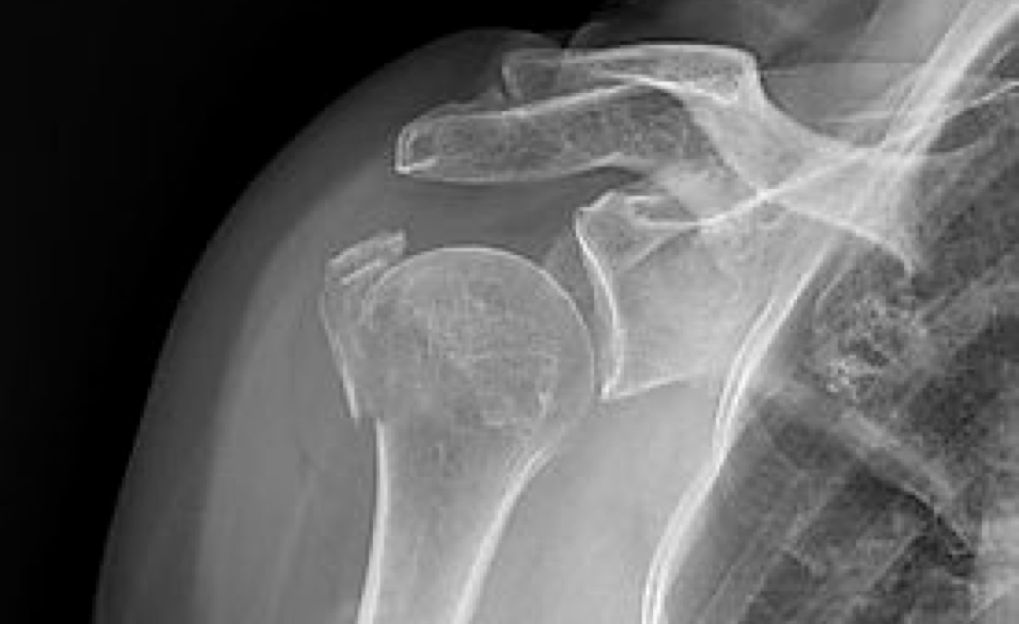

Shoulder radiographs demonstrating a "shoulder separation" or acromioclavicular sprain ("AC sprain"), with the clavicle end elevated away from the acromion (left image), and repair with open reduction internal fixation (right image).